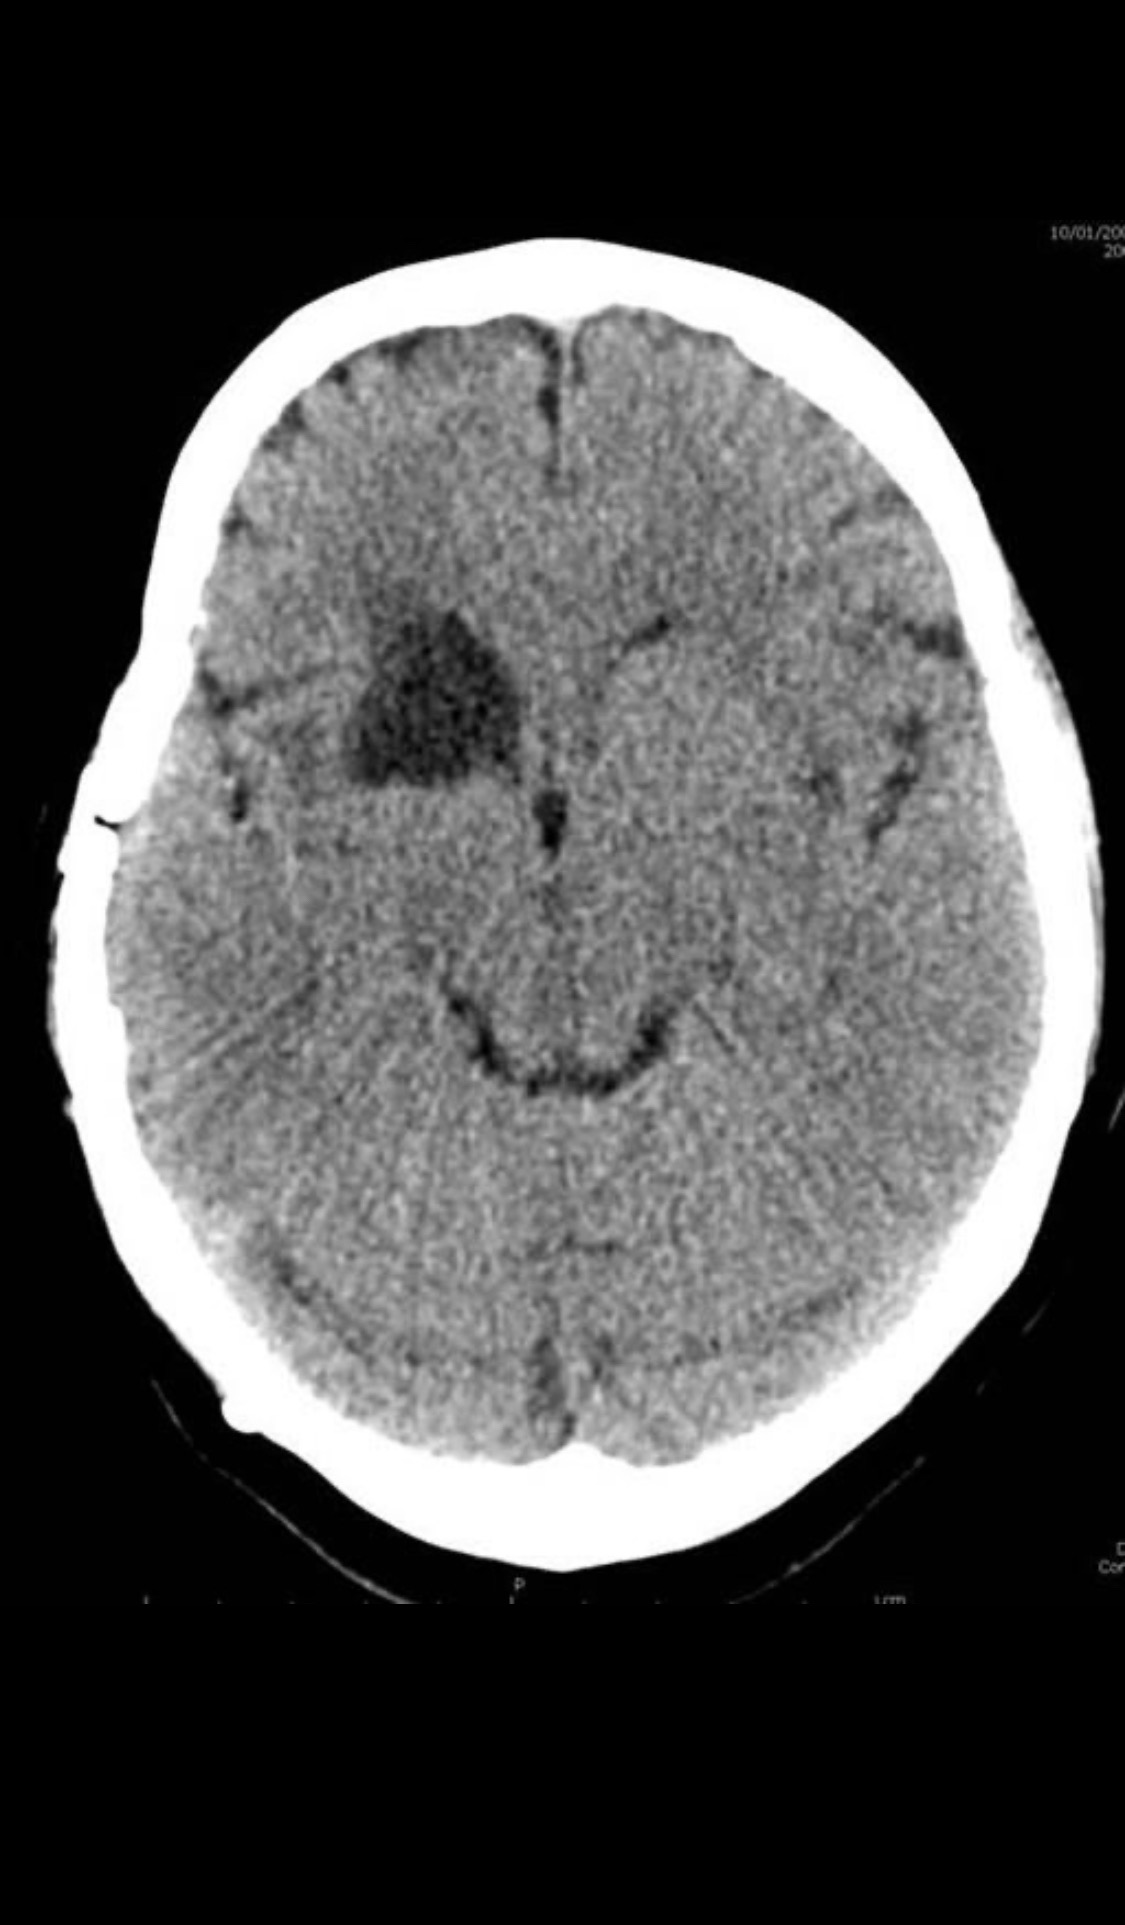

MLS,M79Y,sah,双侧MCA烟雾病,Heubner返动脉瘤,前交通段开窗,细支发出Heubner返动脉,瘤颈细长,瘤颈口比微导管细,弹簧圈2mmx3cm“隔山打牛”填塞治愈,Heubner返动脉保留。

该患者术后2天观察神志清楚,四肢活动正常。